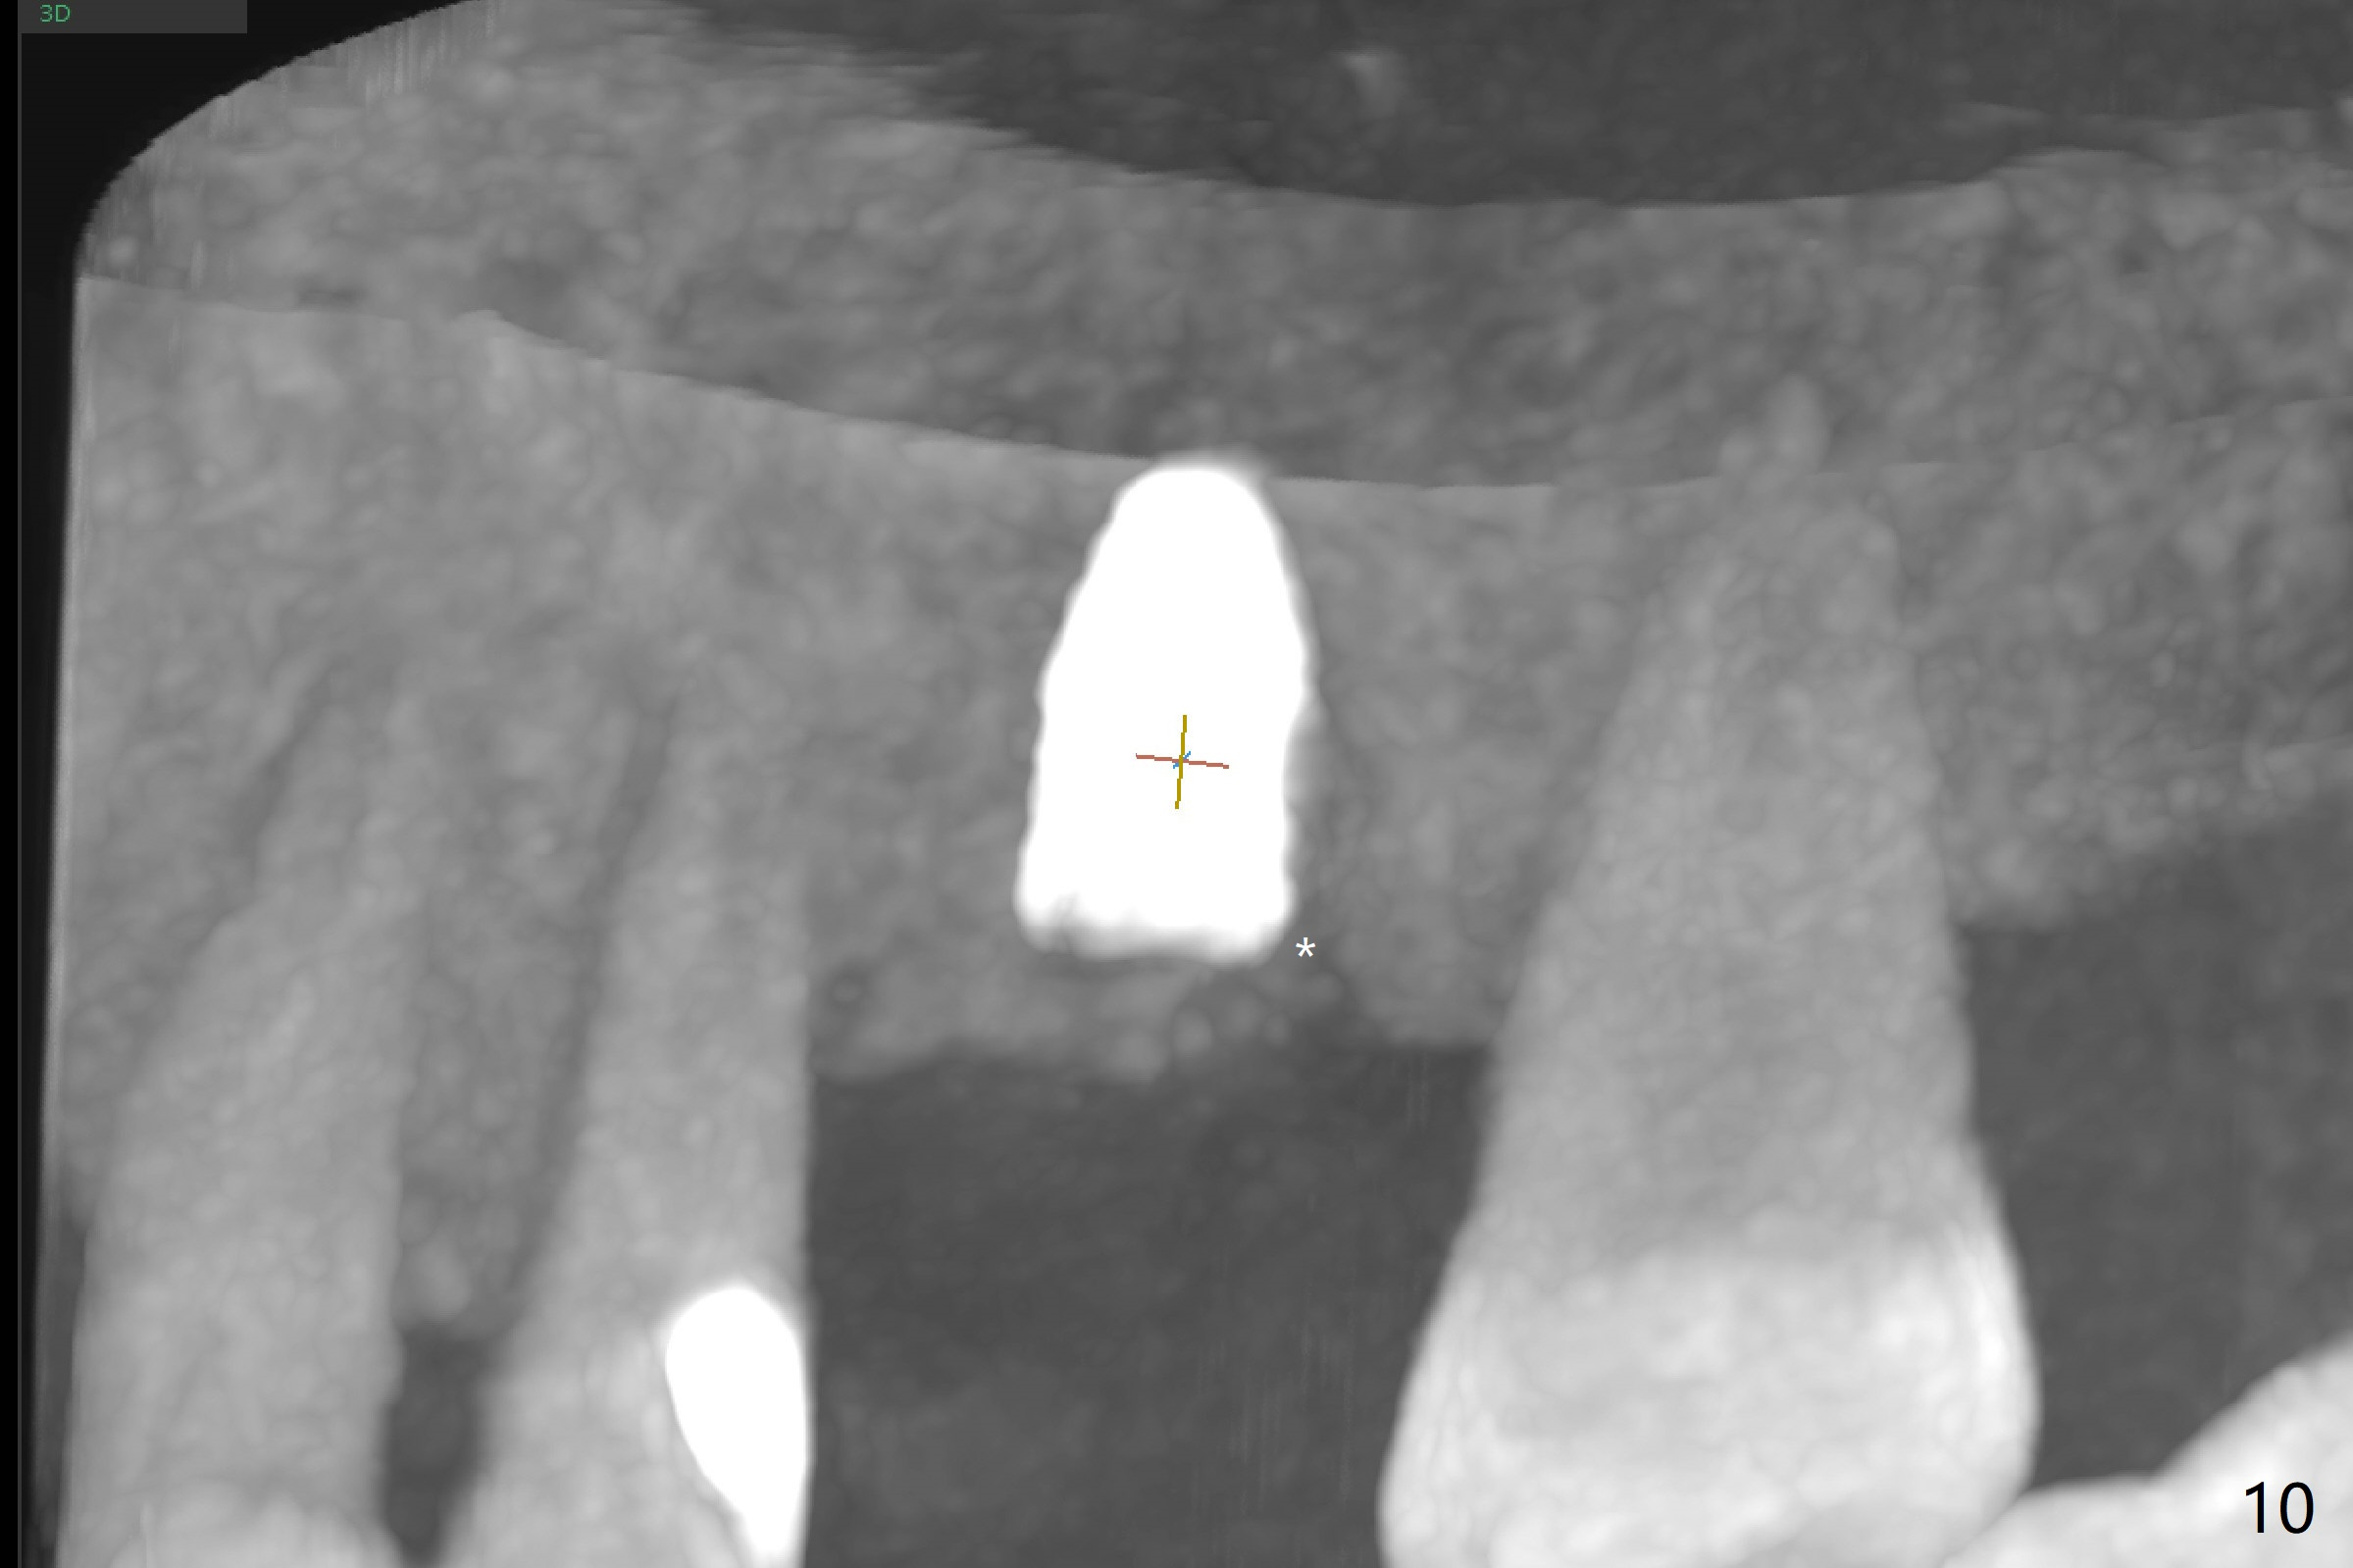

Trajectory of sinus lift without guide at #14 is off (Fig.1 (Magic Sinus Lifter (L) for 9 mm (gingival level)) and needs to be corrected (Fig.2 long line) by re-using 4.8 mm Magic Drill. Following placement of PRF membrane and Demineralized Cortical Allograft (.125-.850 mm) for sinus lift (Fig.3 black dashed line), a 4x10 mm dummy implant is placed with off trajectory. The latter will be fixed by using Lindmann bur to remove the bone distal (Fig.4). The result is less satisfactory with placement of 4.5x10 mm dummy implant (Fig.5). It appears necessary to initiate a new osteotomy (Fig.6 long black line). In fact the result is appealing (Fig.7). The final implant (5x7.3 mm) seems to be placed ideally shown by PA (Fig.8) and BW (Fig.9). Immediately postop CT demonstrates distal defect (Fig.10 *;3-D) and supracrestal placement palatal (Fig.11 P; coronal section). More allograft is then placed in these 2 areas. In all, it is difficult to establish a correct osteotomy without guide. The patient return for uncover 3.5 months postop, although there is a small hole in the middle of the incision (Fig.12). The crown/abutment becomes loose less than 1 month post cementation when the patient chews something tough. It is more related to the unfavorable implant/crown ratio. It is loose again 2 months later. Screw driver is buried inside the abutment with plumber tape. When it is loose for the 3rd time 13 months post cementation, the existing screw driver with a created slot (for retention) is buried without plumber tape after retorque at 35 Ncm (Fig.13). A tissue-level implant should have been used.